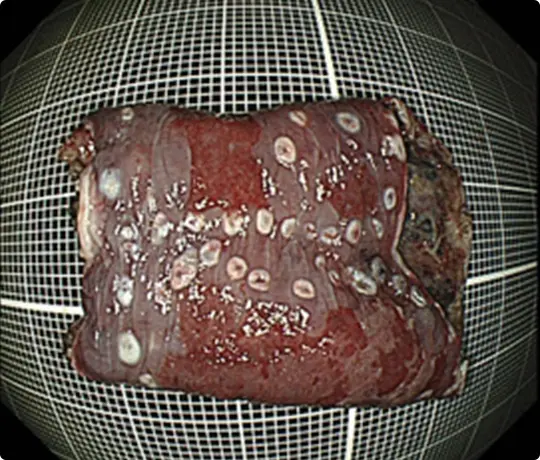

切除した検体をピンで伸ばして、ホルマリンで固定後、病理診断を行います。中央に見える赤く隆起している部分が腫瘍です(青い色素をかけています)。

病理診断で腫瘍は完全に切除されており、治癒と判定されました。

切除した検体です。

切除した検体を展開し、ピンで伸ばしてヨード染色をしています。黄色いところが食道がんの部分です。ホルマリンで固定後、病理診断を行います。病理診断で腫瘍は完全に切除されており、治癒と判定されました。

切除した検体をピンで伸ばしています。ホルマリンで固定後、病理診断を行います。病理診断で腫瘍は完全に切除されており、治癒と判定されました。

切除した検体をピンで伸ばしています。ホルマリンで固定後、病理診断を行います。病理診断で腫瘍は完全に切除されており、治癒と判定されました。